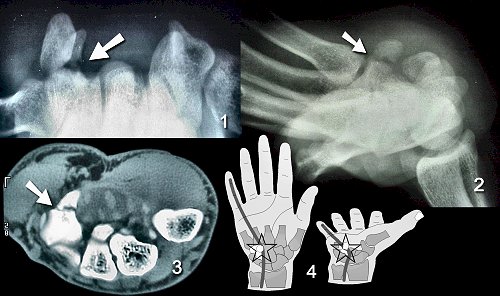

Figure Legend: Hook of hamate fractures

have a high incidence of nonunion (1,2,3). The hook act as a pulley

for the profundis tendon to the small finger, and rough surfaces created

by non-union may result in tendon rupture (4).